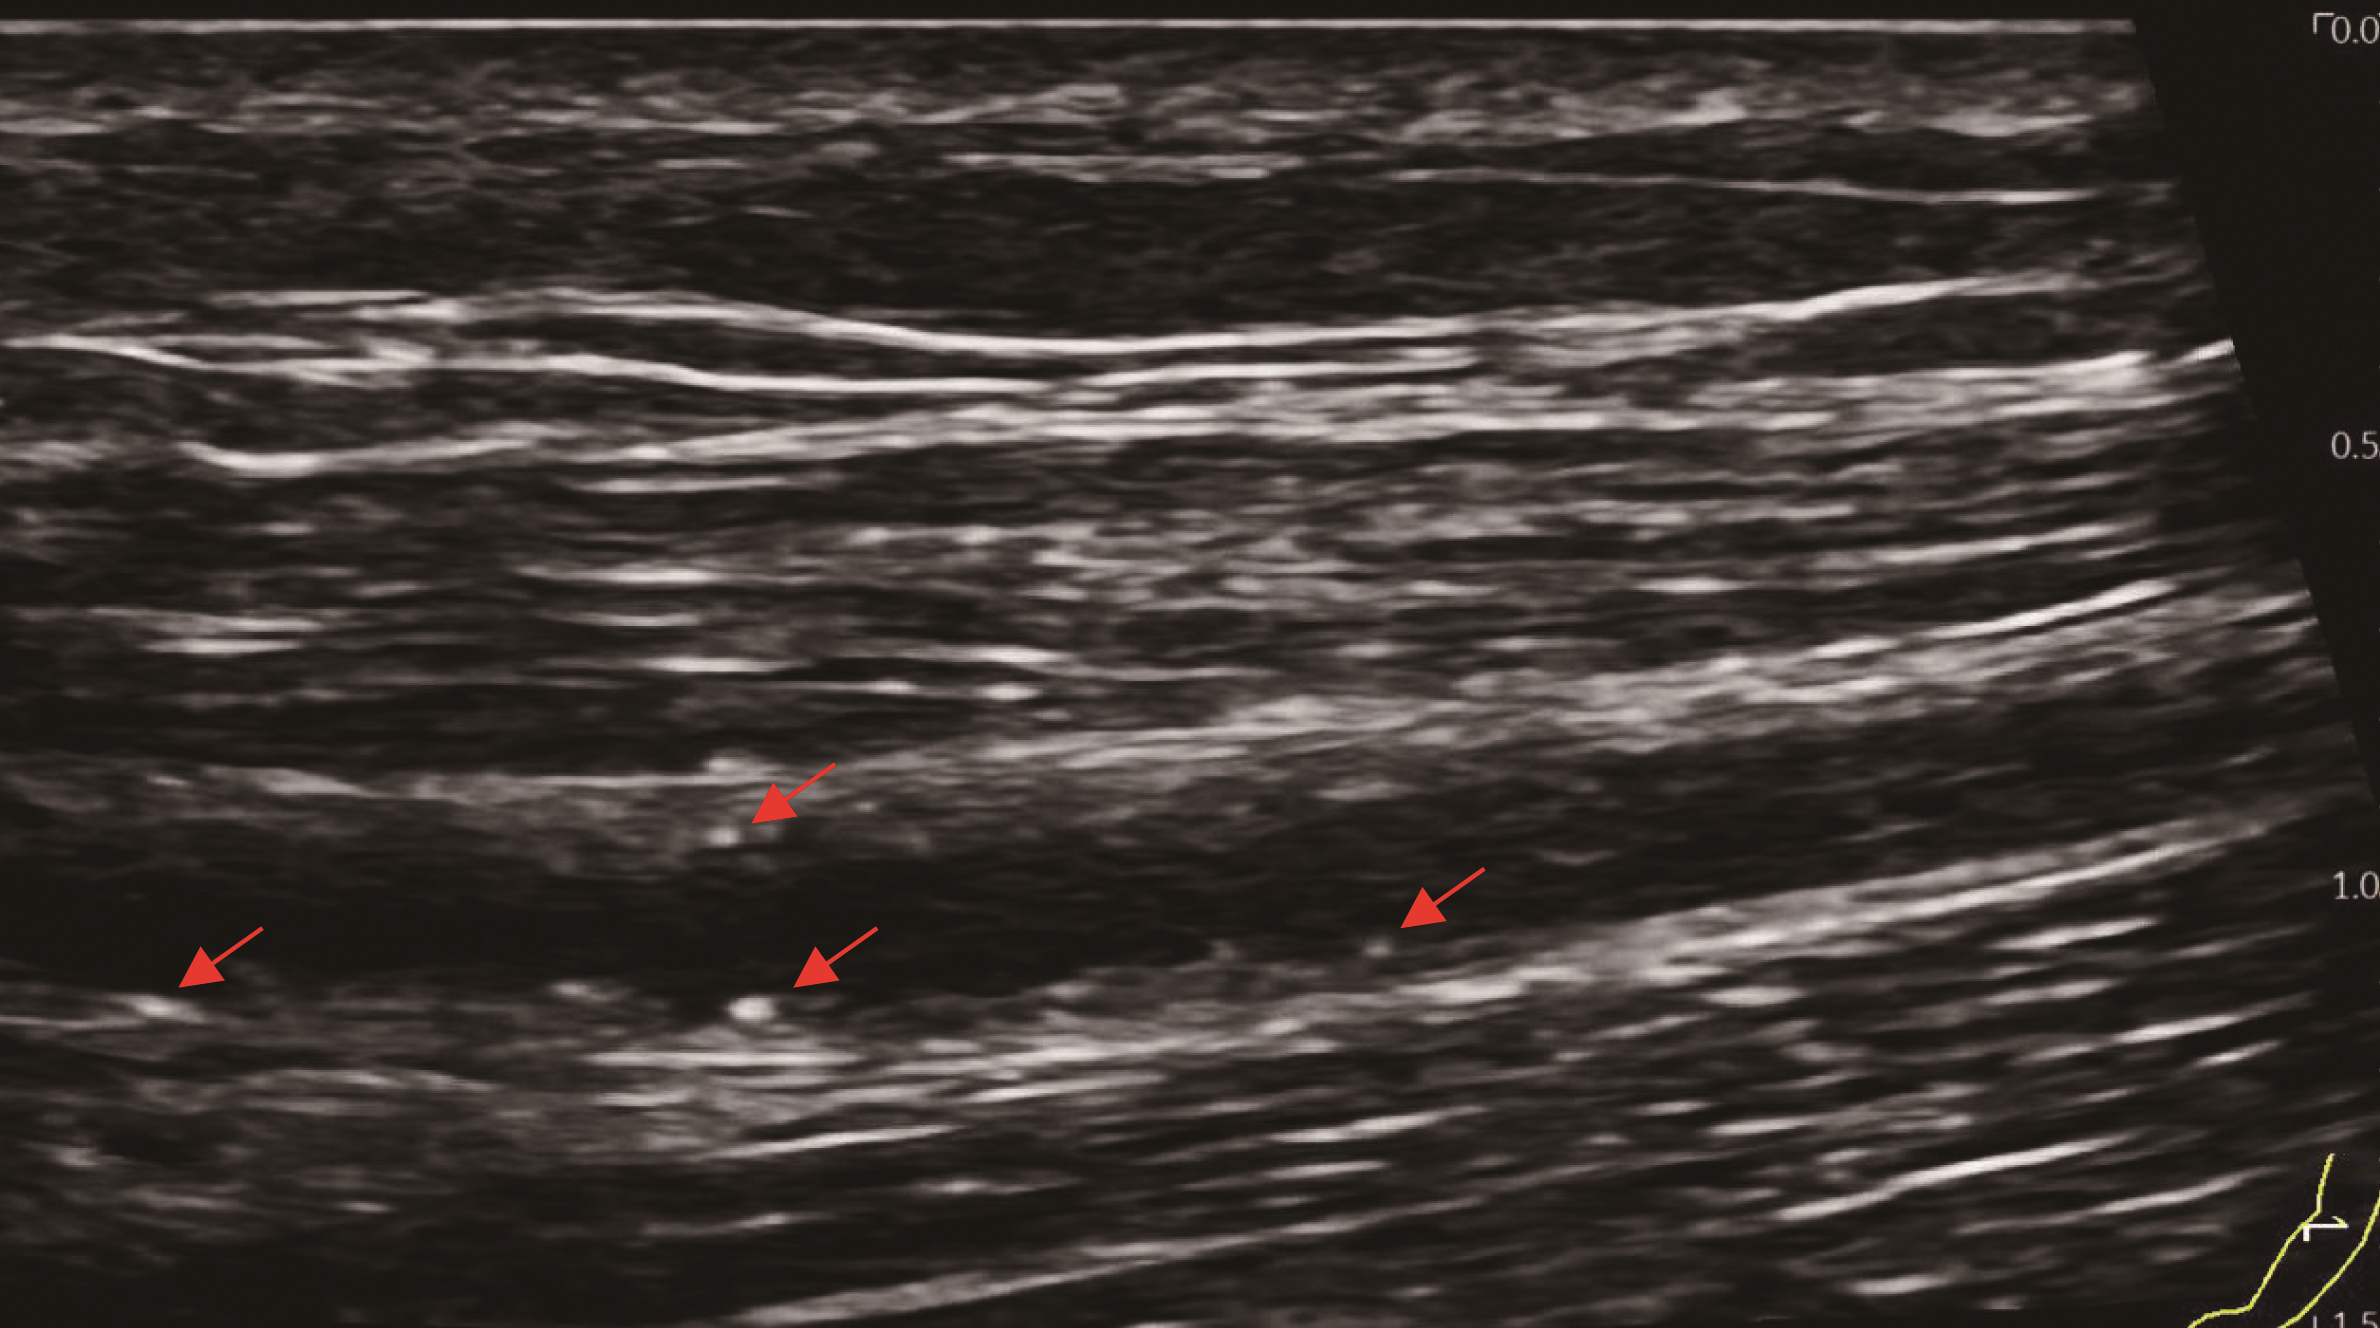

图1 患者动静脉内瘘血管内膜点状钙化斑形成(血管彩超)